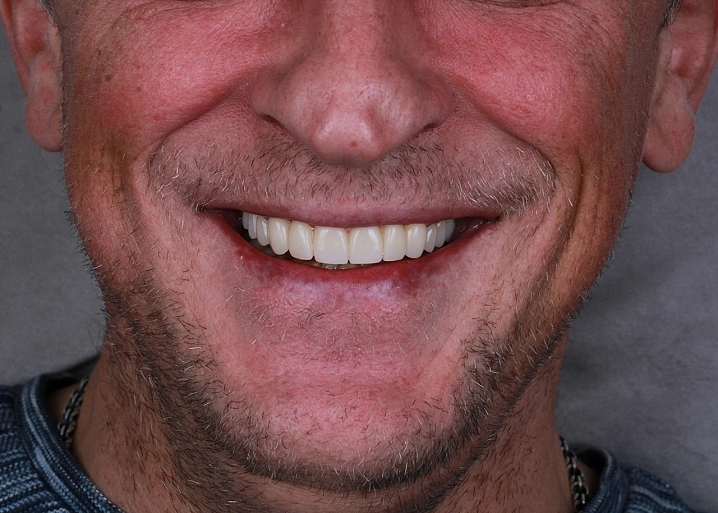

На первичном осмотре в клинике стоматолог определяет степень разрушения зуба. Проводится КТ диагностика для понимания состояния корня зуба, каналов. Фотопротокол для оценки исходной ситуации. Сама консультация проходит в консультативной комнате, где доктор наглядно показывает пациенту его клиническую ситуацию в полости рта и объясняет всё о предстоящем лечении. Определяется из какого материала и каким методом будет изготавливаться будущая вкладка и назначается эндодонтическое лечение каналов зубов, при необходимости. Составляется план лечения.